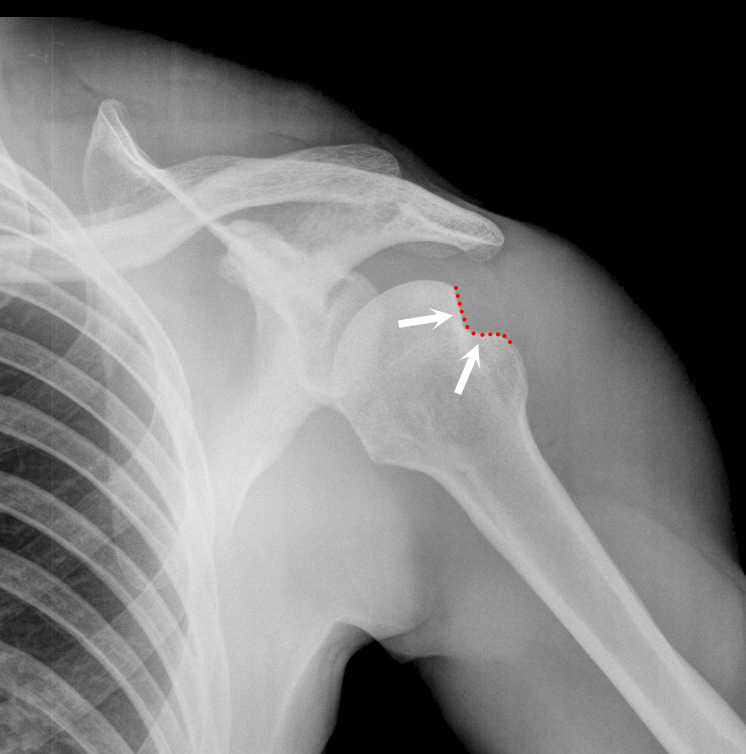

Welche Pathologie sehen sie auf diesem Röntgen der linken Schulter und durch welchen Mechanismus entsteht diese?